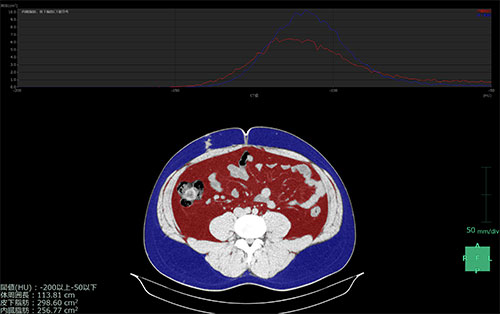

単純CT画像から最適な解析断面の自動検出(臍位置の断面の自動検出)、皮下脂肪、内臓脂肪や骨格筋などの面積を自動的に算出します。算出した結果はレポート保存、出力ができます。

ボリュームデータを用いて体幹部の皮下脂肪、内臓脂肪、骨格筋領域を自動で抽出し、面積や体積の評価をおこなえます。またその結果をグラフとして表示し、スライスごとの脂肪量、部分体積などを確認できます。